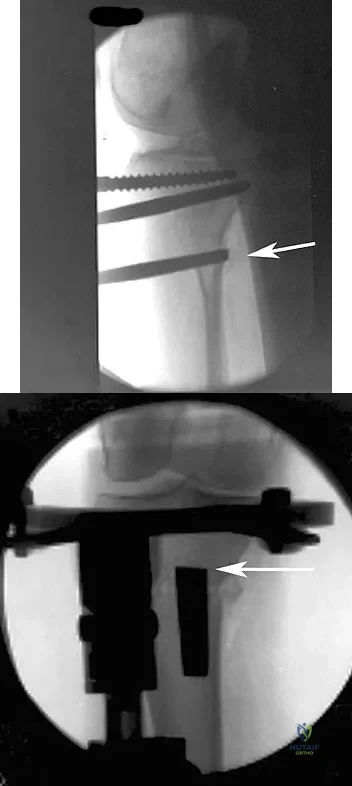

In performing an opening wedge high tibial osteotomy at the tibial tubercle, the osteotome extends 5 mm posteriorly and centrally out of the bone as shown in Figures 17a and 17b. What is the first structure it enters?